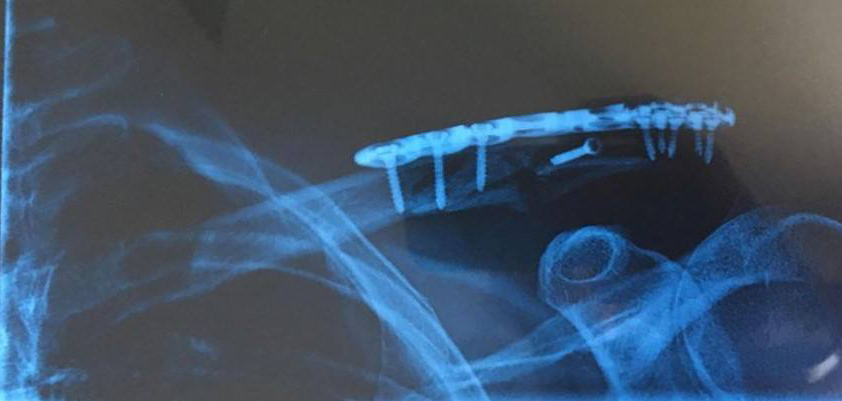

Finally out of surgery at 10pm on Wed night. To be honest it’s been a rough 24-36 hours since then, but now finally on the mend. The surgeon certainly had his work cut out for him, installing 9 screws and a titanium plate. Luckily he had all the parts as Bunnings had already closed. It’s just a shame they don’t use carbon fibre (much lighter and more aero), and had I thought about it beforehand, I would have insisted they install a Garmin mount on the plate. Thanks heaps for all your messages of support, and of course to Megs who has been my 24-hour resident nurse.